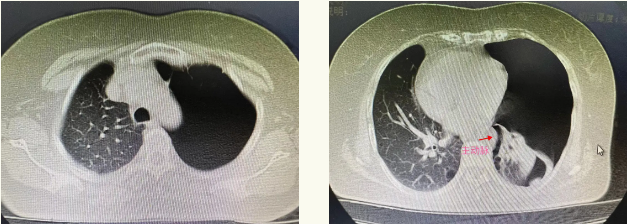

术前CT

患者胸部CT示患者左肺多处肺大泡病损组织,胸腔广泛粘连,其中1处成串肺大泡与人体最粗的主动脉严重粘连且范围较广,稍有不慎可能造成大出血,手术风险高且难度较大。在排除手术禁忌症后,经过充分的术前讨论,最后决定采用国内最先进的单孔胸腔镜技术进行手术。由王天舒副主任主刀,与信国玺主任、李鑫医生、麻醉科孙志勇医生密切配合下顺利完成手术。手术切口仅为3cm,术中采用了电凝及钝性游离,腔镜闭合器楔形切除法、环烧法、结扎法及生物胶覆膜固化法多种手术技巧。采用肋间神经阻滞封闭减少术后疼痛及美容缝合(无需拆线),微管引流。